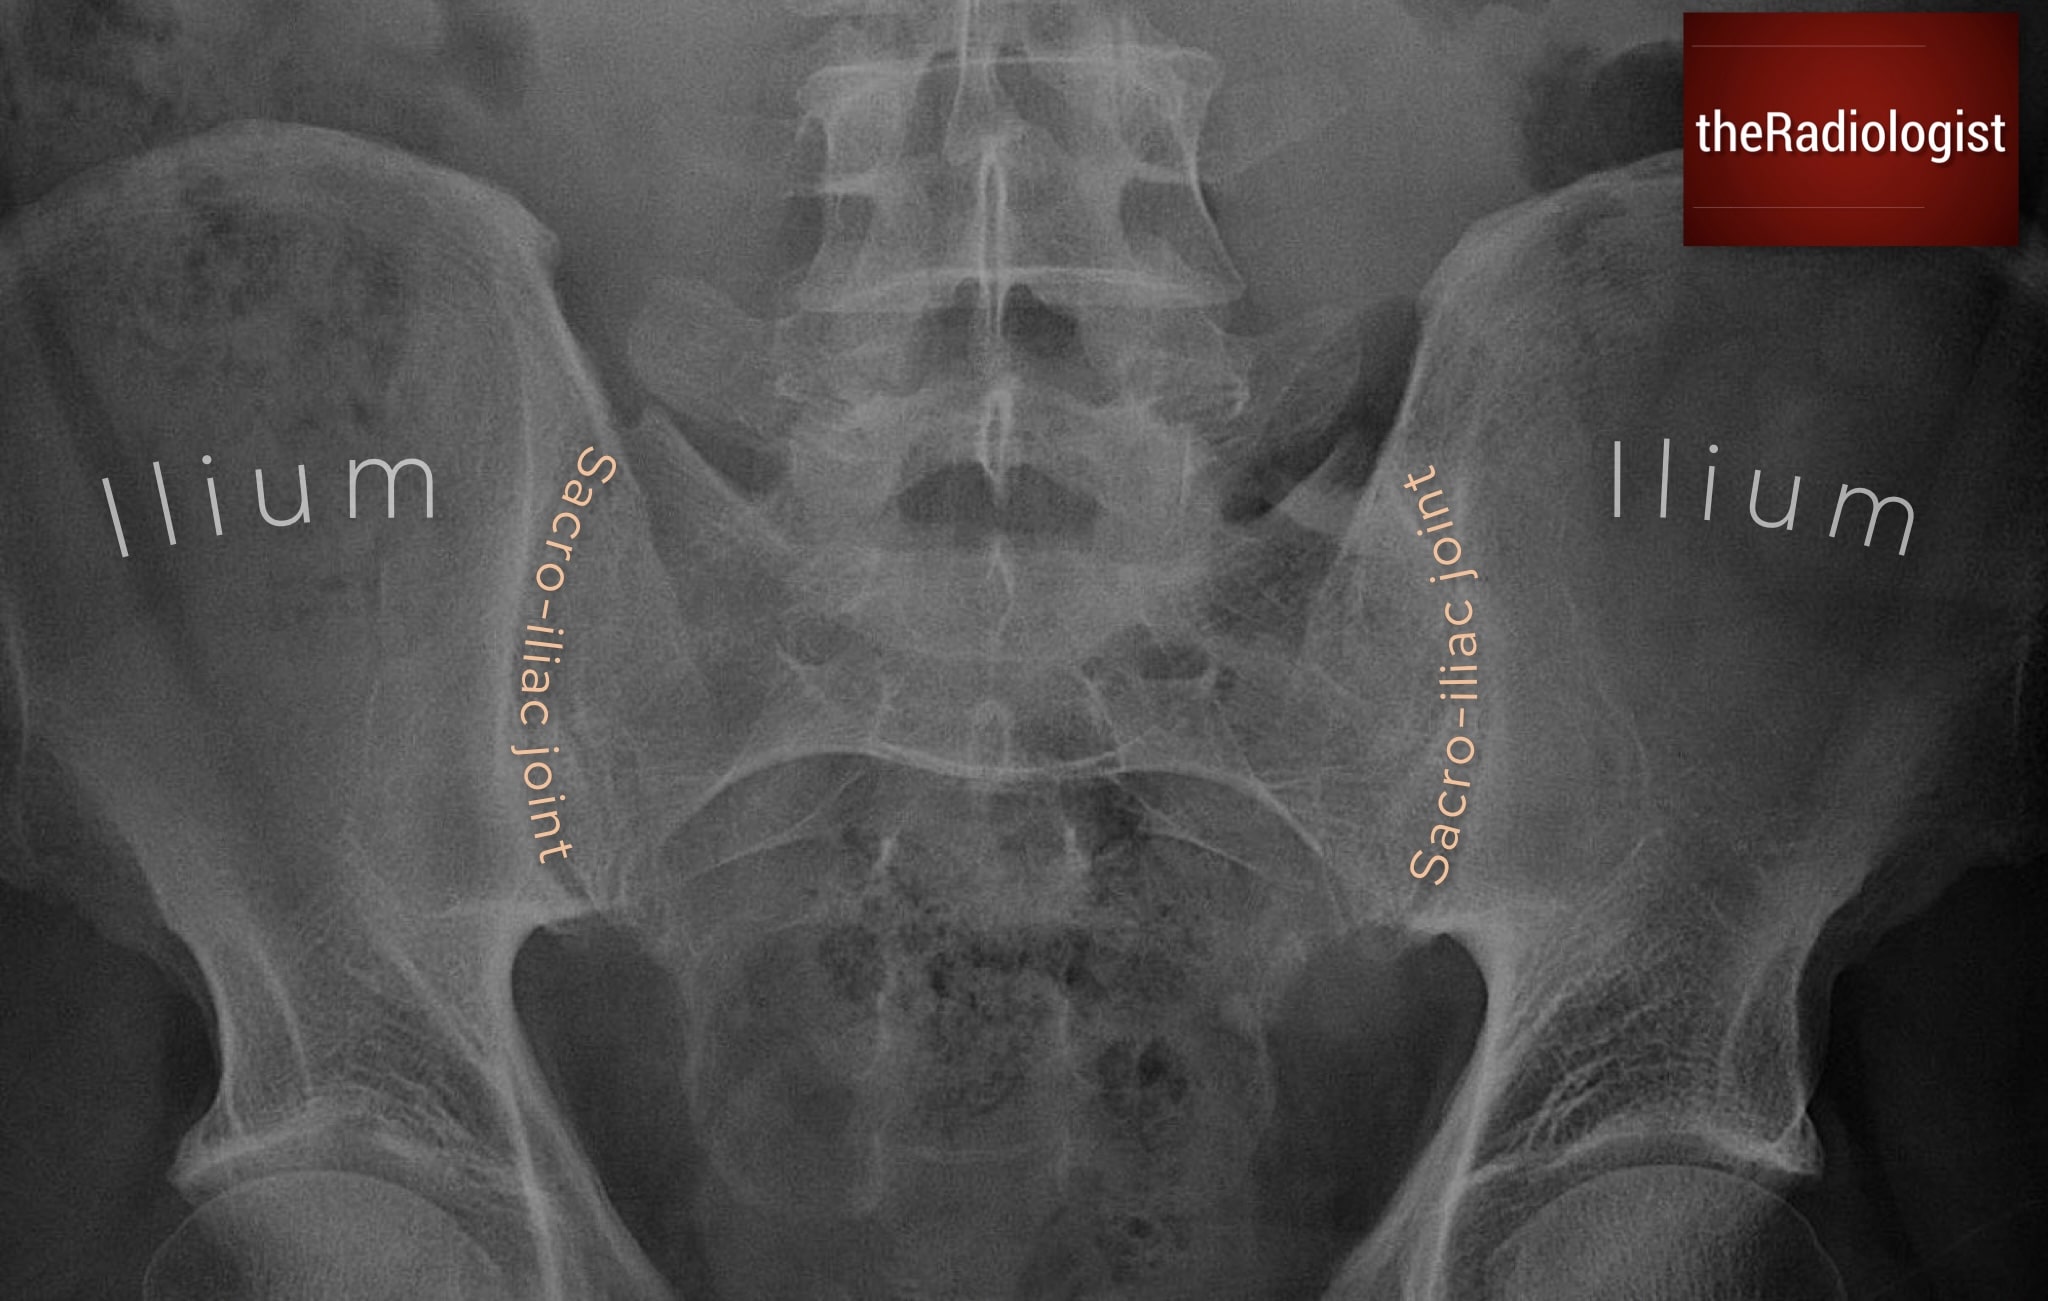

S: Sacroiliac joints

Inspect both sacroiliac joints for symmetry. Widening or displacement can indicate acute trauma although this is not as common as chronic changes. Chronic bilateral sclerosis or ankylosis can be seen in osteoarthritis and seronegative spondyloarthropathies. MRI is best for early inflammatory change, but on plain film we can see more advanced changes.

Check the sacro-iliac joints checking for widening, narrowing, ankylosis or sclerosis.